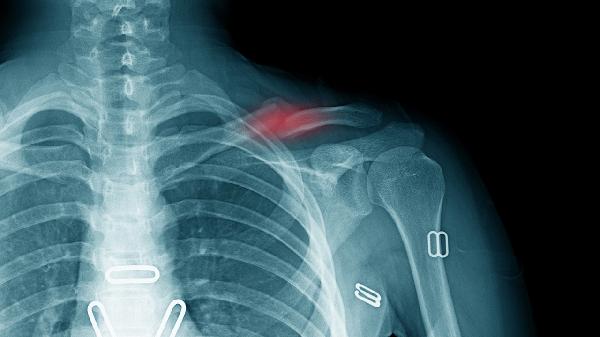

颈部疼痛多位于锁骨上方或肩胛骨内侧区域,可能放射至肩部或头部。这种疼痛常由斜角肌紧张或颈肋压迫神经血管引起,姿势不良或长时间伏案工作可能诱发或加重。疼痛性质多为钝痛或刺痛,转动颈部时可能加剧。建议保持正确坐姿,避免长时间低头,可通过热敷缓解肌肉紧张。若疼痛持续或伴有头晕等症状,应就医检查。